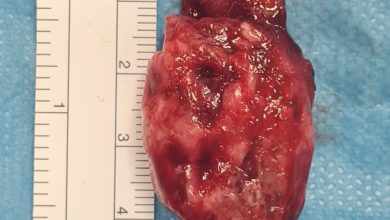

جراحو تبوك يعيدوا بناء فك مريض بطباعة ثلاثية الأبعاد

نجح فريقٌ طبيٌّ سعوديٌّ متخصصٌ في جراحة الفم والفكين في مستشفى الملك فهد التخصصي بتبوك، في إعادة بناء الفك لمريض…

نجح فريق طبي في مستشفى النور بمكة المكرمة بإجراء عملية جراحية لواحدة من أندر الحالات الطبية وأكثرها غرابة وهي “متلازمة…

أكمل القراءة » -